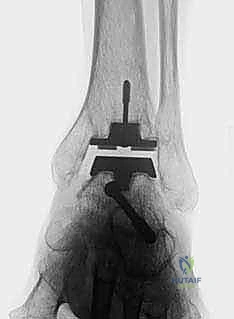

TECH FIG 5 • Subtalar arthrodesis. A. Postoperative AP view with subtalar arthrodesis using a single OA cancellous screw.

TECH FIG 5 • Subtalar arthrodesis. B. Lateral view.